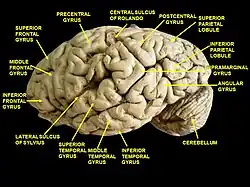

Cerebrum. Lateral view. Deep dissection. Superior temporal gyrus is visible at the center. | |

Position of superior temporal gyrus (shown in red). Lateral view of a human brain, main gyri labeled.